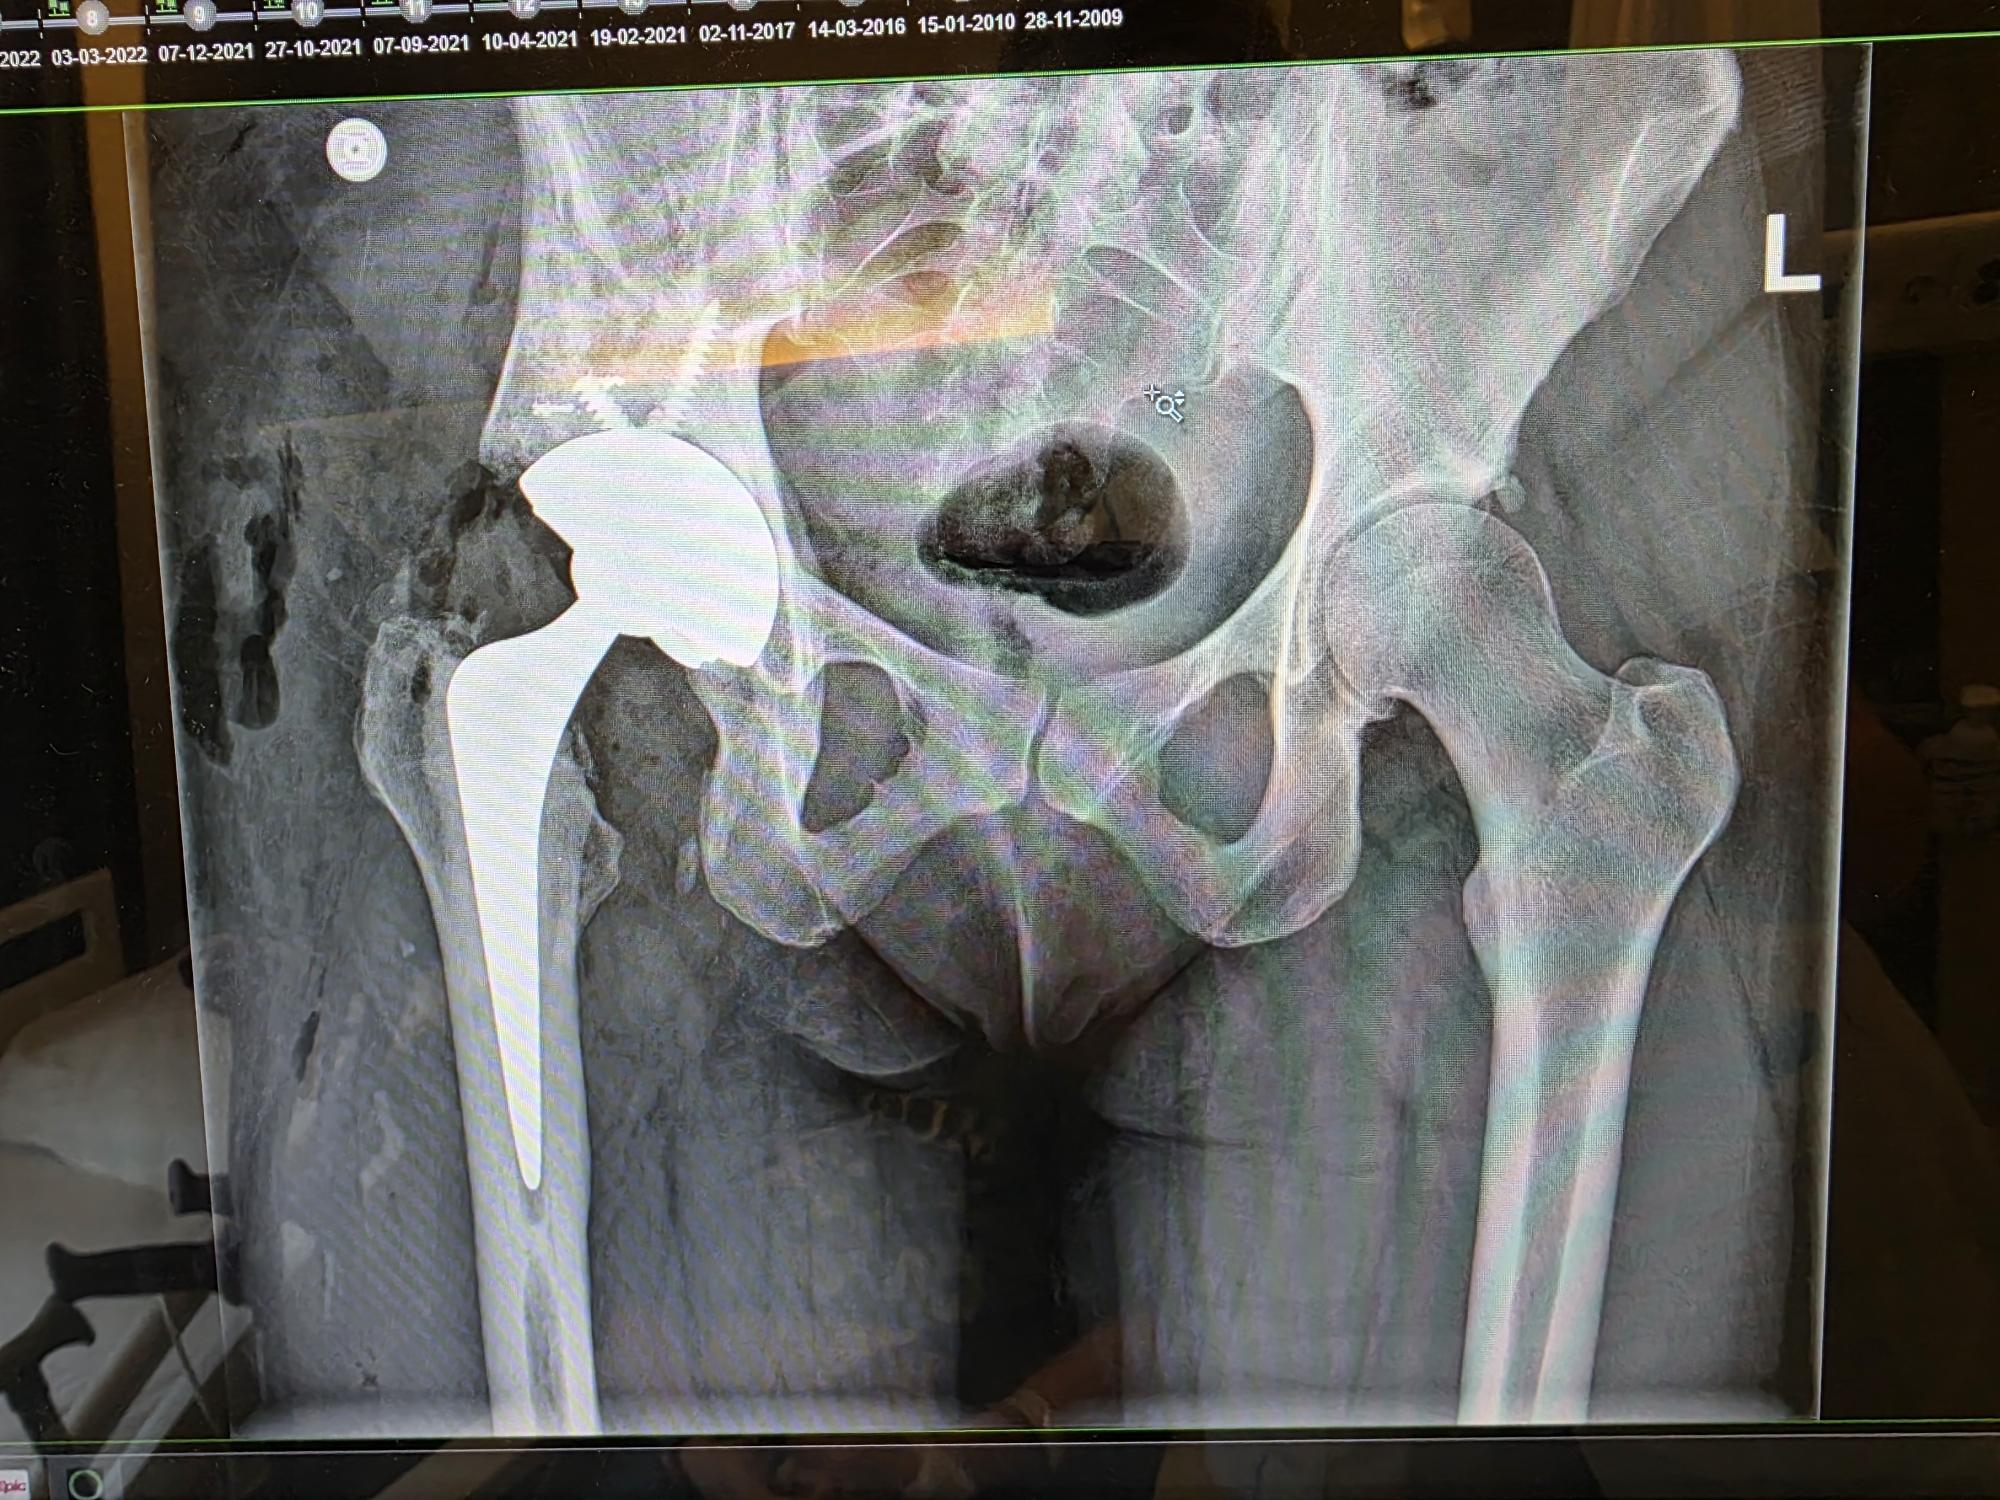

Then the physio came and she observed that I knew it all already. π As was to be expected. She was pleased with the results. Back in the room, I had to get to the bed, so they could take me to radiology. The xrays went fast too, as I knew what to do there as well.

There was also good news on the new cup! With the one they used now, I don't have to be 100% off my leg for 6 weeks. With the physio, I am allowed to make a plan to get into the rehab bit by bit... Yay! But it also means I can do some more things a bit easier on my own. π

Hopefully @Altbot can help me with this xray snap.